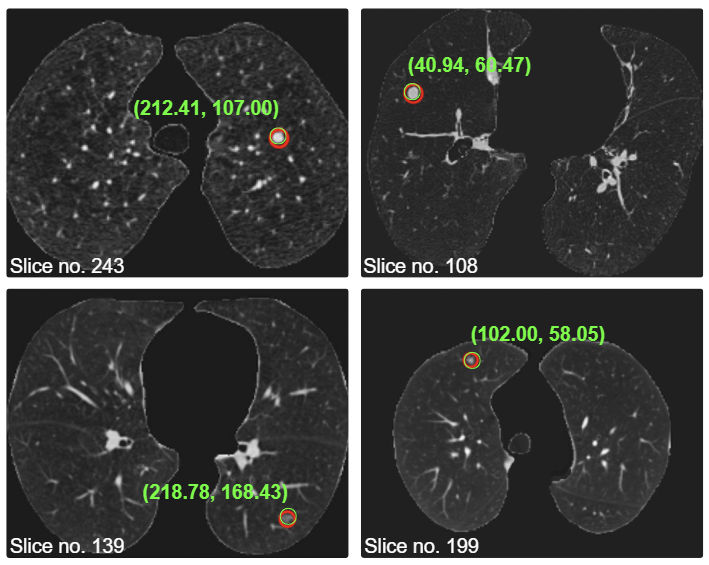

Lung cancer is the leading cause of cancer mortality worldwide, responsible for roughly one in five cancer deaths. In Bangladesh, it ranks among the most consequential cancers, placing third for new cases and second for cancer deaths in 2022. We focus on analyzing low-dose chest CT scans to automatically detect pulmonary nodules, including small or subtle findings that can be difficult to identify during routine review. By using 3D deep learning models that capture the spatial structure of lung nodules, our work aims to reduce radiologists' workload while improving the sensitivity of early cancer screening.

Beyond detection, we also study how AI can help determine whether a nodule is likely to be benign or malignant by learning from both its visual texture and its underlying CT intensity patterns. This allows us to move from simply finding nodules to providing more informative, risk-aware decision support for follow-up and diagnosis.